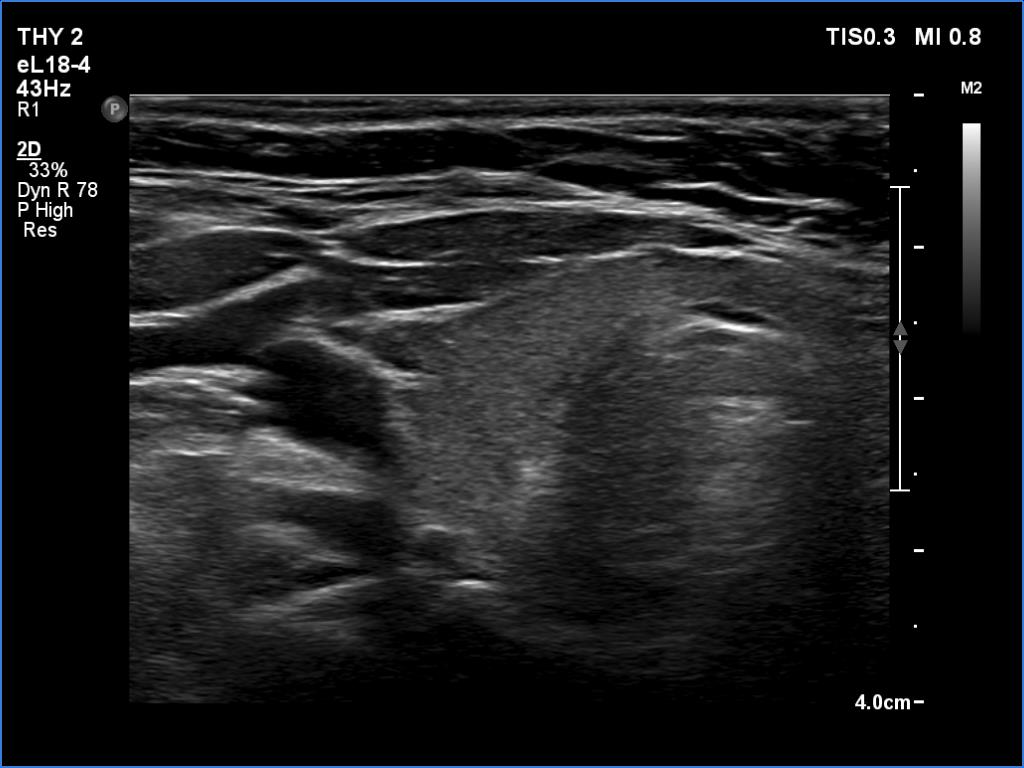

Second examination 2 years later (third rows of images):

Clinical data: The patient had no complaints.

Palpation: Both lobes were a bit firm on palpation. There was a not firm nodule in the right lobe.

Laboratory tests: TSH 2.05 mIU/L on daily 50 microgram levothyroxine.

Both the ultrasound and the cytological patterns remained unchanged.

Comments. The discrete lesion in the left lobe is highly suspicious, and even after two reassuring cytological findings, some suspicions remain. Two considerations. Firstly, the largest diameter of the lesion was 10 and 9 mm, first and second examination, respectively. All TIRADS are contradictory on the indication of cytology: according to their main tables, cytology is not justified, while all argue in the text that cytology may be considered in the case of a nodule with a suspicious sign no larger than 1 cm. Secondly, ultrasound follow-up is clearly advisable in such cases.